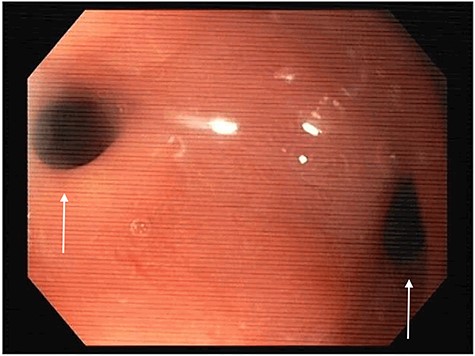

At the 24-month follow-up, an upper endoscopy confirmed integrity of the stomach pouch and GJA without any GGF (see Fig. 10). Thirty-six months after surgical treatment of the GGF, the patient remains asymptomatic and has a stable BMI.

Esophagogastroduodenoscopy image showing a normal gastric pouch with only one orifice corresponding to the gastro-jejunal anastomosis (arrow).